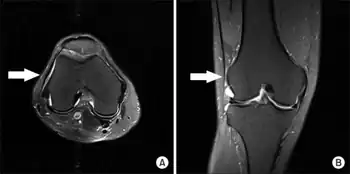

Diagnosis of iliotibial band syndrome is based on history and physical exam findings, including tenderness at the lateral femoral epicondyle, where the iliotibial band passes over the bone.[10]